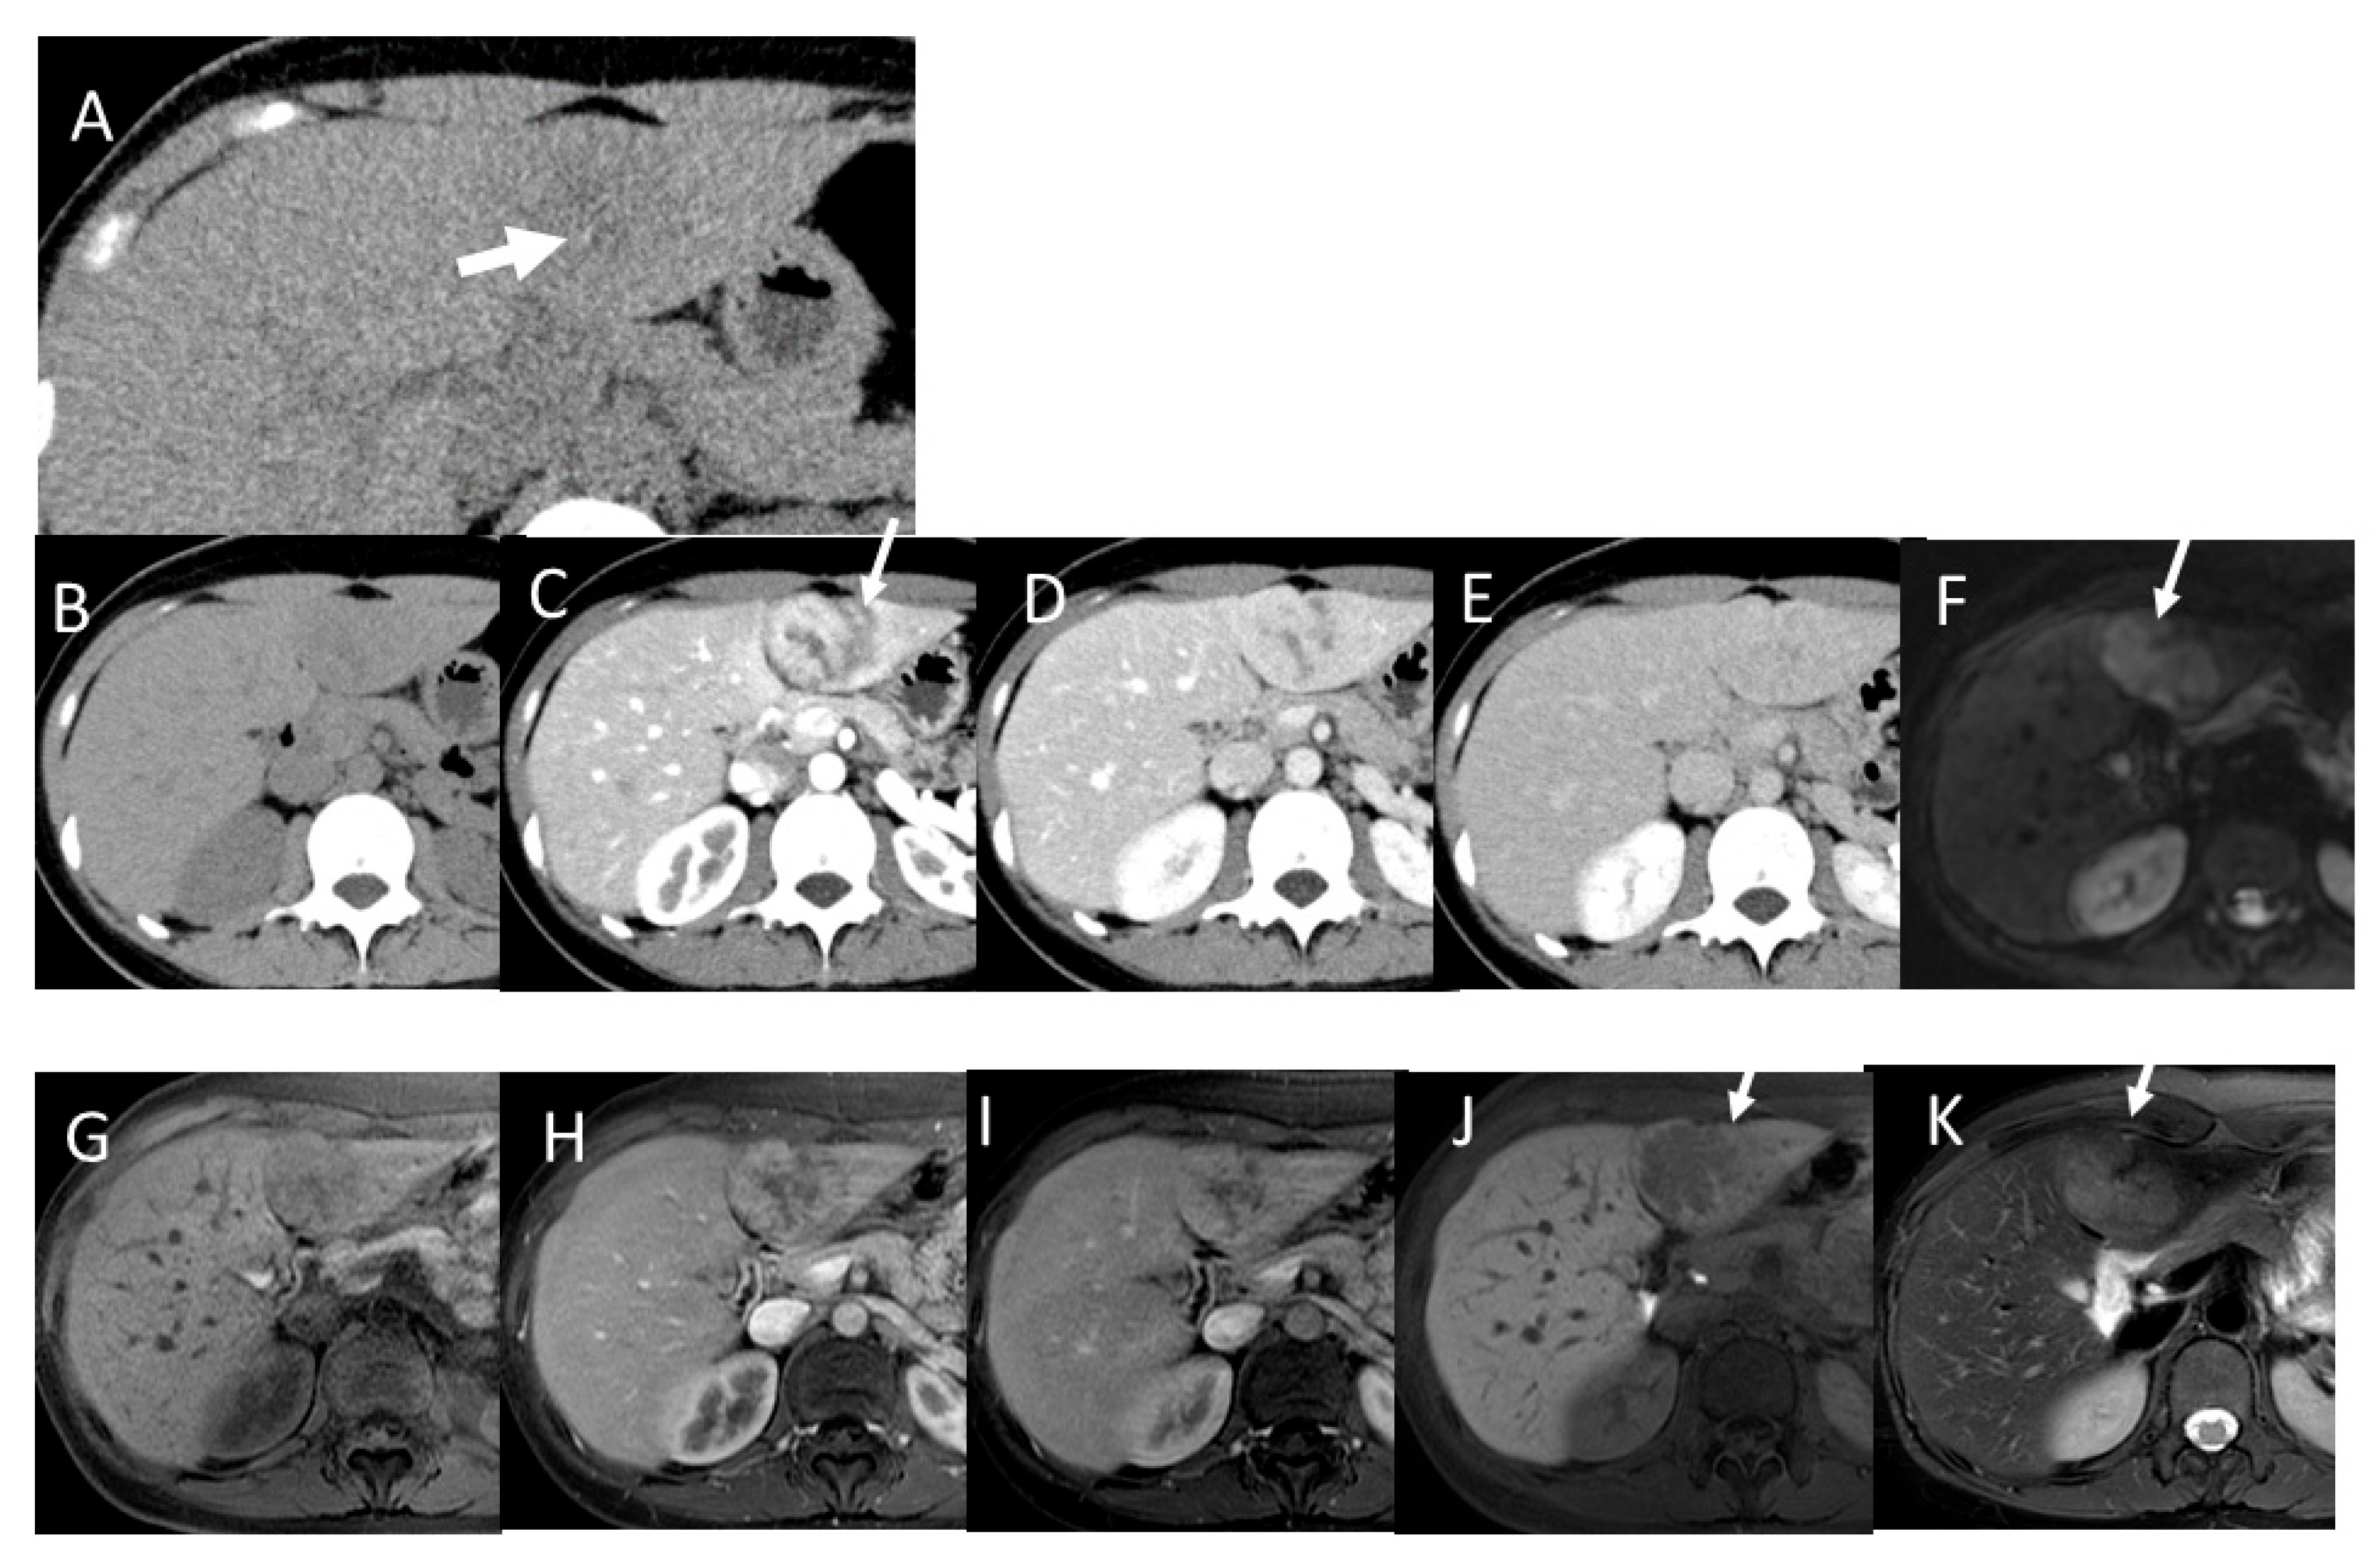

4.6. Fibrolamellar Hepatocellular Carcinoma (FL-HCC)

4.7. Combined Hepatocellular and Cholangiocarcinoma (cHCC-CCA)